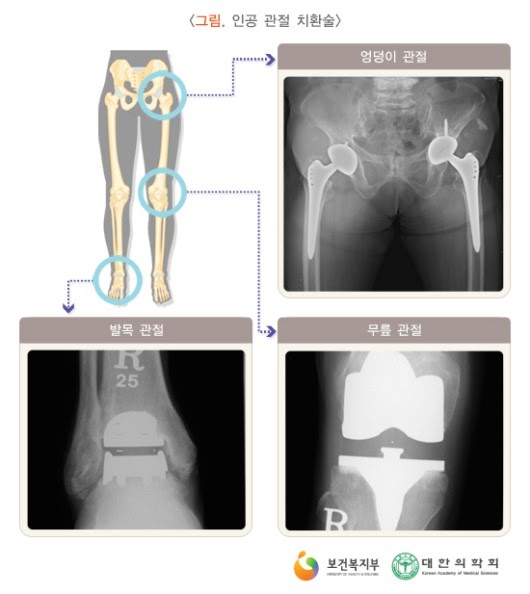

보다 심한 관절염에서 고려되는 방법으로, 인공 관절 치환술이 대표적이고 효과적인 방법입니다. 손목이나 발목 관절의 퇴행성 관절염에 대해서는 경우에 따라 관절 고정술이나 자가 조직을 이용한 관절 성형술이 고려되기도 합니다.

*마모와 파손, 감염, 해리, 불안정성 등의 합병증으로 인공관절은 수명이 있을 수 밖에 없고, 재치환술은 피할 수 없습니다. 인공관절 재치환술은 수술 술기도 어려울 뿐만 아니라 그 결과도 일차 치환술에 비하여 떨어지는 한계가 있습니다.